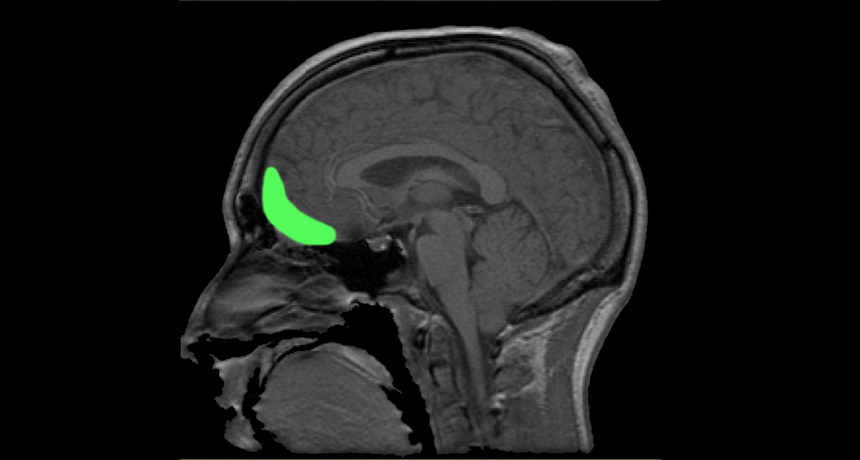

6. What is the gyrus rectus?